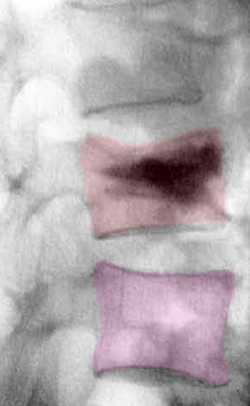

Διαδερμική κυφοπλαστική, ακτινοσκόπηση. Η ειδική βελόνη εισέρχεται διαδερμικά στο σώμα του σπονδύλου (φούξια βέλος) και γίνεται έκπτυξη μπαλονιού το οποίο ανατάσει το οστεοπορωτικό κάταγμα (αριστερά). Κατόπιν πραγματοποιείται έγχυση ακρυλικού πολυμερούς στο σώμα του σπονδύλου για να σταθεροποιηθεί το αναταχθέν κάταγμα (δεξιά). |

Κάταγμα 01 (φούξια) με μείωση του ύψους του σπονδύλου σε σύγκριση με τον υποκείμενο υγιή σπόνδυλο (μπλέ)(αριστερά). Κυφοπλαστική με ανάταξη του κατάγματος και επαναφορά του ύψους του σπονδύλου στο φυσιολογικό (δεξιά). |